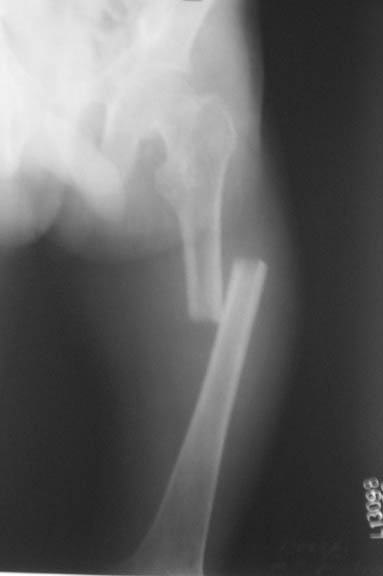

This patient,a middle aged malewas a diagnosed case of hypophosphatemic osteomalacia on treatment. Unfortunately he discontinued treatment since he was poor and also neutral phosphate was not available locally. He presented with pathological fracture of left femur and a failing neck of same femur.

We managed to get neutral phosphate, initiated medical treatment and did an antegrade SIGN nailing of left femur along with couple of screws to neck using miss a nail technique. He complained of pain of the right femur and both forearms. In OT these areas were screened using image intensifier and found that he has looser zones of all these with impending fractures. Yesterday we did a retrograde nailing of right femur usingSIGN nail. Both ulnas were stabilised usingLambrudini wires in a closed fashion. All fractures and looser zones were stabilised by closed surgery using image intensifier. It may be interesting to see the post of picture of both the hips in which one side shows an antegrade femoral SIGN nail and the other side shows a retrograde SIGN nail.